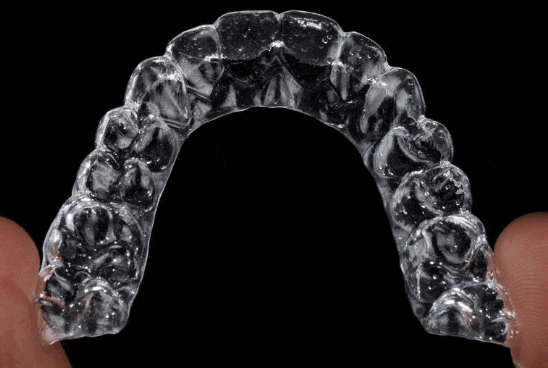

요즘 투명교정 인기가 정말 뜨겁습니다.

심미성과 편리함이라는 장점에 많은 분들이

나도 !! 투명교정으로 치료하고싶다!! 원하고 계세요.

그런데 투명교정은 알고 있는것과 같이

꼈다 뺐다하면서 사용하는 것인데요.